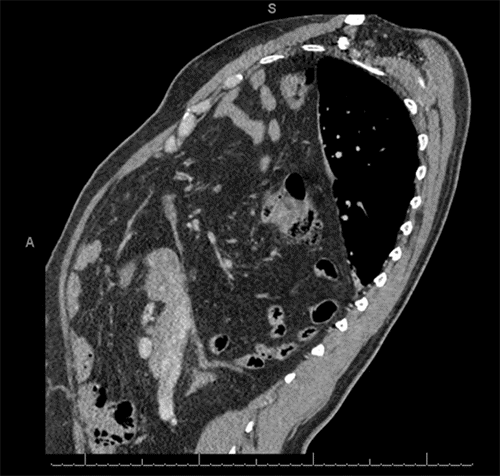

We present the case of a 50-year-old male with a remote history of a repaired left congenital diaphragmatic hernia in infancy and chronic obstructive pulmonary disease requiring 2 liters/minute of supplemental oxygen (with no history of tobacco use). He presented with chronic shortness of breath, dyspnea on exertion, and orthopnea. Pulmonary evaluation led to a chest computed tomography (CT) scan, which revealed an exceptionally large right diaphragmatic hernia containing significant portions of the liver, mesenteric fat, and loops of both small and large bowel herniated into the right hemithorax (Figure 1). He was subsequently referred for thoracic surgical consultation for diaphragmatic hernia repair.

Figure 1. Preoperative CT of Large Right Diaphragmatic Hernia. Published with Permission

Axial views from a preoperative CT scan of the chest and abdomen. Note a large right-sided diaphragmatic hernia with substantial herniation of abdominal contents, including segments of the liver, mesenteric fat, and loops of small and large bowel, into the right hemithorax